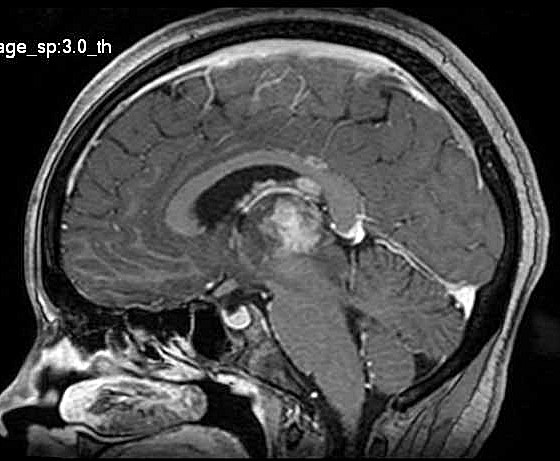

| Fem. 17a. |

| Nódulo sólido homogêneo preenchendo o III ventrículo, com limites precisos, com hipossinal em T1 e hipersinal em T2 e FLAIR, que se impregna por contraste paramagnético. Lesão menor implantada no assoalho do IV ventrículo provavelmente representa disseminação por via liquórica. |

| SAGITAIS, T1 SEM CONTRASTE | T1 COM CONTRASTE | |

| F. 17a. Tumor teratóide rabdóide atípico de III ventrículo. RM | HE | VIM, GFAP | HHF35, desmina, 1A4 | AE1AE3, EMA |